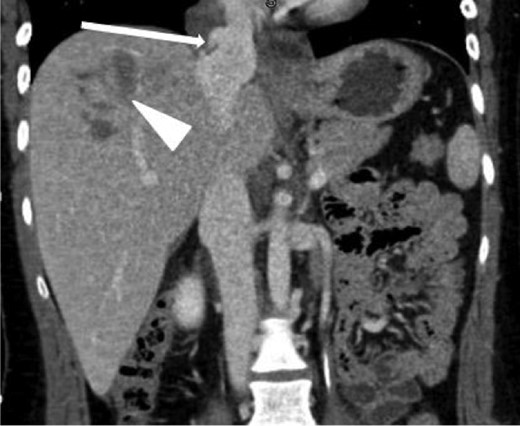

Coronal contrast-enhanced CT of the chest showing abnormal contour of the supradiaphragmatic IVC with ventrally and laterally confined contrast extravasation (arrow) consistent with a pseudoaneurysm surrounded by pericaval hematoma as well as a segment 8 hepatic hypodensity consistent with liver laceration and focal area of contrast extravasation (arrowhead).

Coronal contrast-enhanced CT of the abdomen performed 30 min after the initial CT of the chest showing persistence of the abnormal contour of the supradiaphragmatic IVC with contrast extravasation confined laterally and ventrally (arrow), nonexpanding pericaval hematoma and a segment 8 hypodensity (arrowhead) consistent with liver laceration.